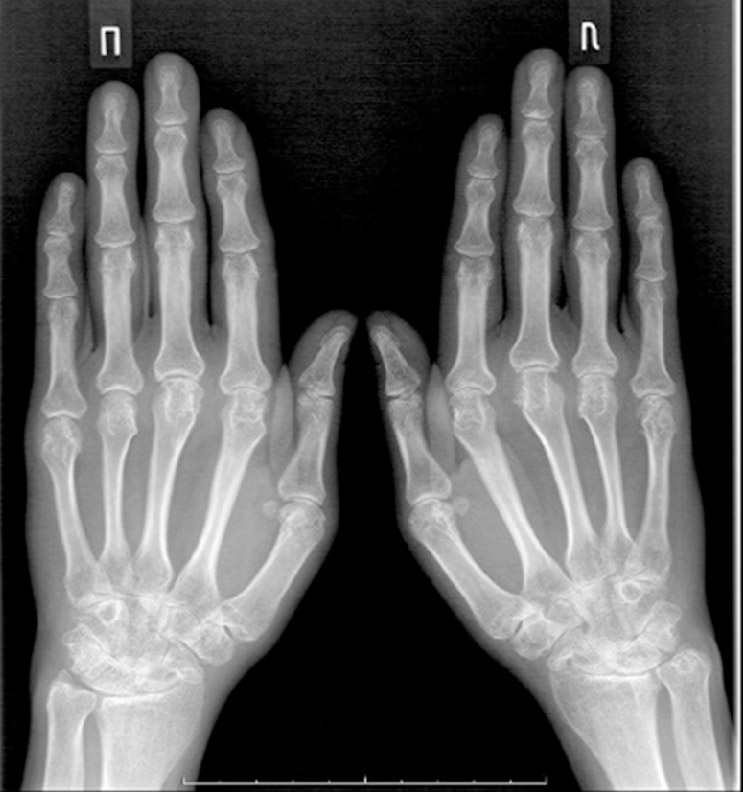

Рентгенологическая стадия поражения запястья определялась по классификации Larsen 1977 г. [12], которая в зависимости от степени сужения суставных щелей и выраженности костной деструкции включает пять стадий поражения суставов запястья. Согласно классификации Larsen, пациенты распределились следующим образом: у 8,7% была II стадия поражения суставов запястья, у 31,9% – III стадия, у 42,0% – IV стадия, у 17,4% – V стадия (рисунки 1–3).

Рисунок 1. Рентгенологическая картина начальных стадий поражения суставов запястья и деформаций кисти.

Figure 1. X-ray pattern of early stages of wrist deformities.